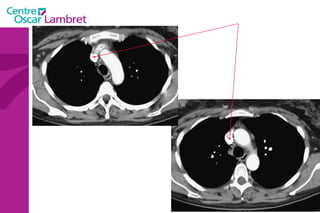

Le médiastin C'est l’espace au centre du thorax. Il est situé en avant de la colonne vertébrale et peut être divisé en plusieurs quadrants.  Il est divisé, par convention, en : médiastin postérieur :  contenant notamment  l’oesophage et l’aorte descendante.  médiastin moyen :  contenant les voies aériennes supérieures : trachée et sa division (carène).  médiastin antérieur :  contenant le cœur, l’aorte ascendante, les artères pulmonaires et la veine cave supérieure.

Le médiastin C'estl’espace au centre du thorax. Il est situé en avant de la colonne vertébrale et peut être divisé en plusieurs quadrants. Il est divisé, par convention, en : médiastin postérieur : contenant notamment l’oesophage et l’aorte descendante. médiastin moyen : contenant les voies aériennes supérieures : trachée et sa division (carène). médiastin antérieur : contenant le cœur, l’aorte ascendante, les artères pulmonaires et la veine cave supérieure.

Le médiastin Le  médiastin moyen  comprend : La trachée La carène Les pédicules pulmonaires : Les bronches souches Les veines et les artères pulmonaires Le segment horizontal de la crosse de l’aorte Le Tronc Artériel Brachio-Céphalique L’artère carotide primitive gauche La crosse de la grande veine azygos